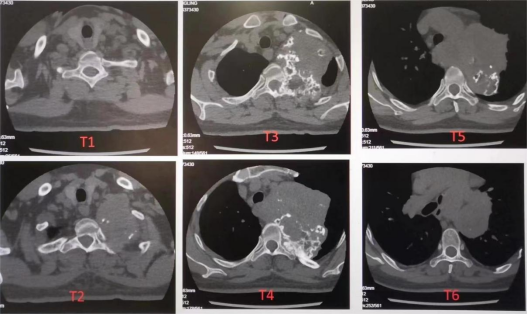

来自贵州的江女士17年前体检发现左上后纵膈占位,近年来肿物明显增大,压迫周围重要脏器和脊髓,影响肢体功能,危及患者生命。江女士辗转多家医院后,均表示肿瘤切除难度太大,为求进一步治疗,江女士来到了华西医院胸外科马林副教授门诊就诊。经胸部CT检查显示,患者纵隔肿块横跨左侧胸1-6椎旁,最大截面约10.6x9.5cm,肿瘤性病变可能性大,肿块内多发高密度影,来源于软骨可能,周围血管、气管及食管受压,左侧锁骨下动脉略包埋、变窄,胸3-4椎体左侧、左侧第3、4肋骨近段破坏。

7个小时后,手术顺利结束,术后患者返回重症监护室继续治疗,予以患者积极抗感染、呼吸支持、镇痛、镇静、祛痰、营养支持治疗、维持水电解质平衡及对症支持治疗,术后第一天便拔除气管插管,顺利转回胸外科病房,复查胸部CT,术后恢复正常,无继发肺部感染及其他并发症,经多学科医护团队共同协作,目前患者术后恢复良好,已正常进食,自理能力已恢复。